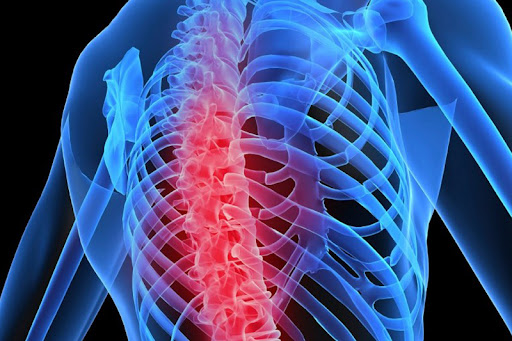

Aşırı zayıf, hareketsiz bir yaşam tarzına sahip ve kortizon kullanmış kişilerin kemik erimesi açısından risk altında olduğunu vurgulayan Endokrinoloji ve Metabolizma Hastalıkları Uzmanı Dr. Esra Tutal, “Kemik erimesi omurlarda, el bileğinde ve kalça kemiğinde kırılmalara yol açarak sakatlıklara, hatta ölümlere yol açabilir” dedi.

Halk arasında ‘kemik erimesi’ olarak adlandırılan osteoporozu ‘kemiklerin zayıflayarak kırılgan hale gelmesi’ şeklinde tanımlayan Liv Hospital Samsun Endokrinoloji ve Metabolizma Kliniği’nden Uzm. Dr. Esra Tutal, hastalığın kemiklerin çok ufak travmalarda bile kolayca kırılmalarına neden olabildiğini söyledi.

Konuyla ilgili önemli bilgiler paylaşan Uzm. Dr. Esra Tutal, osteoporozun kırık gelişine kadar hastalarda hiçbir belirti vermeyebileceğini işaret etti.

Kemik erimesine bağlı kırıkların en çok kalça, bel ve bilek kemiklerinde görüldüğünü vurgulayan Uzm. Dr. Esra Tutal, “Osteoporoz hem kadınları hem de erkekleri etkileyen bir hastalıktır.

Kemik erimesi çok ileri dönemlere kadar herhangi bir belirti vermez. İleri dönemlerde ise sırt ağrısı, bel ağrısı, boyun zamanla kısalması ve duruş bozukluğu (kamburluk) meydana gelir” diye konuştu.